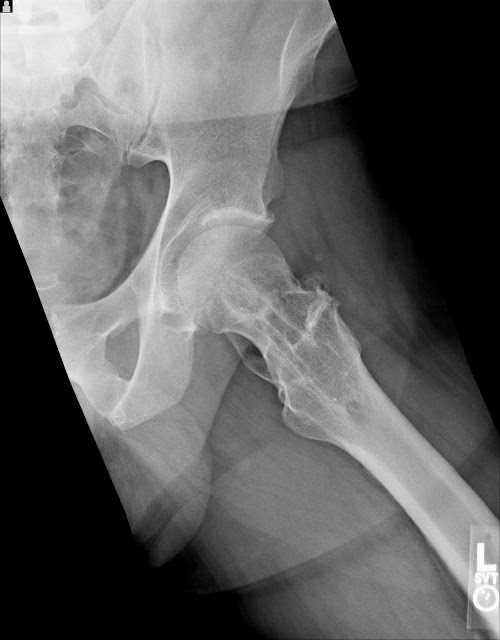

All the X-rays in this post were taken a few months ago, the ones from the time of the accident are much worse. Someday I will post the comparisons of before and after, the differences are quite amazing.

I had broken the ball of the hip joint completely off which was put back together with a rod which was later removed. This is how it looks now.

In this view you can see all the additional bone and even where the rod used to be.